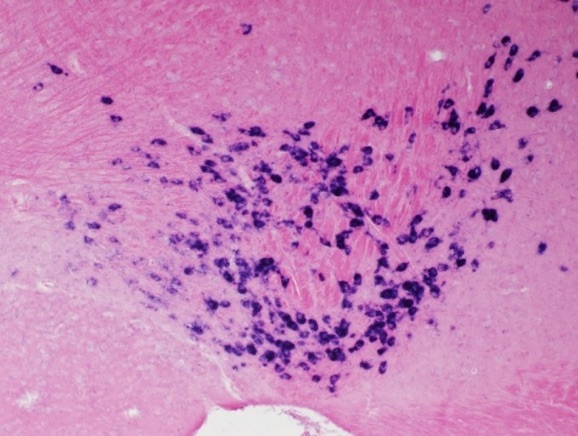

マウスVTA。ドパミン神経特異的に発現させた外来遺伝子のISH。DIG-AP-NBTのISHでは、シグナルは青紫色になる。赤はNuclear

Fast Redによるcounter sitain